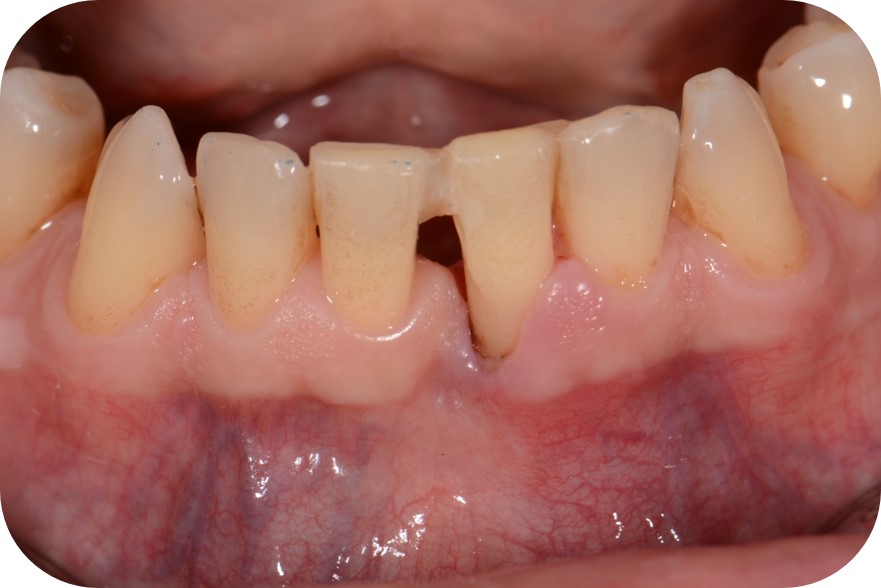

10/12 - Clinical situation 3 months post-operative with 5 mm probing pocket depth.Two-wall intrabony defect treated using cerabone® and Straumann® Emdogain® - Dr. D. Rakasevic & Prof. Dr. S. Jankovic